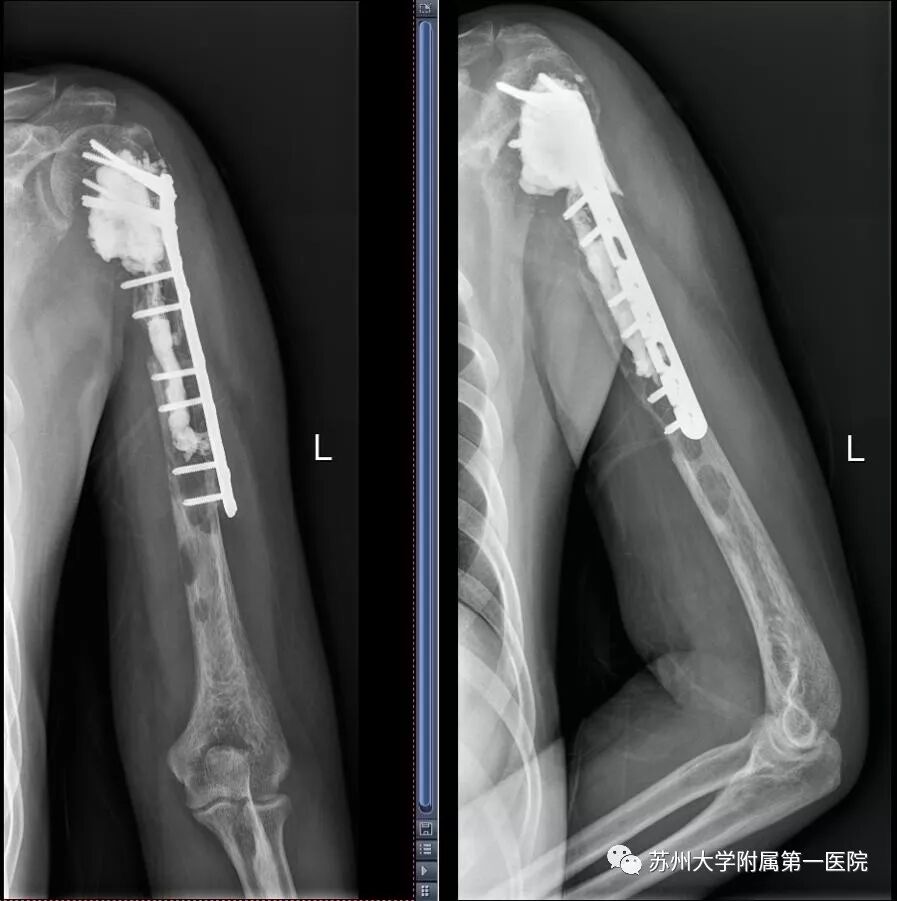

术后一年复查X线片显示肿瘤未见复发,假体位置好

2019年底,距离方大叔手术已经过去一年。在这一年里,方大叔平均每两个月来复查一次,检查结果都非常好。前两天,他再次进行了术后的复查,复查结果显示肿瘤未见复发,假体位置好。现在肢体功能也已经恢复了90%以上,除了不能提重物以外,可以说已基本步入正常生活。